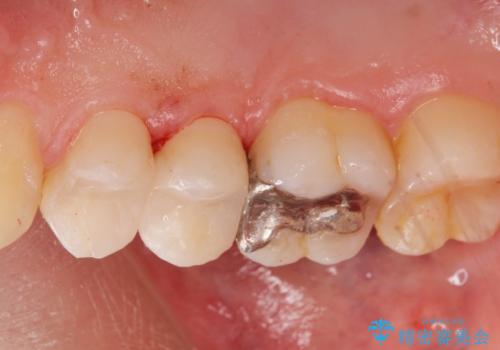

- 定期検診でレントゲンを撮影したところ虫歯があったので拡大鏡下で虫歯を取り除き、白い詰め物にて治療しました。

無事歯の神経を取らずに白い詰め物で治療する事ができました。